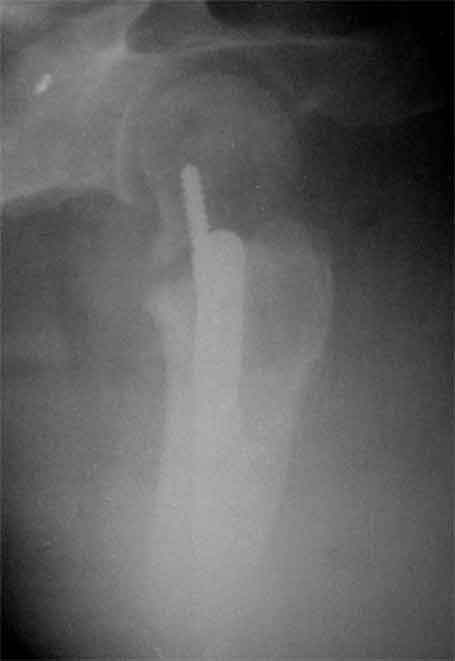

Доброго время суток, коллеги. Обратилась на консультацию пациентка 52 лет. травма и первичный остеосинтез перелома бедра около года назад, далее был обнаружен перелом шейки бедра (возможно ятрогенный), реостеосинтез реконструкционным гвоздем 8 месяцев назад. Конченость не опорна. В больнице, где выполнялись эти вмешательства предложили выполнить THR с длинной ножкой. Возможно ли в такой ситуации добиться сращения шейки при помощи каких-либо остеотомий?

возраст как раз далеко не преклонный, да и головка выглядит "живой"

На мой взгляд дистальный перелом срощен, а состояние тазобедренного сустава и молодой возраст пациентки позволяют произвести вальгизирующую остеотомию проксимального бедра. В случае, если нет сращения дистального перелома можно фиксировать длинным DHS; Если есть сращение- обычным DHS.

> На мой взгляд дистальный перелом срощен,

Вряд ли, сохраняется боль при попытке опоры на конечность,да и по Р -нет уверенности

Коллкега на представленных снимках имеется ротационная стабильность и плохо репонированный перелом. В данный момент думать об эндопротезтровании или межвертельной остеотомий рано, так как перелом диафиза бера еще полностью не сросся, я думаю, надо на данном этапе попытаться стабилизировать перелом шейки бедра конюлированными винтами, удалить проксимальный винт, попытатся сделать репозицию, хотя маловероятно, что получется добиться улучшения, и стабилизировать 3 конюлированными винтами и дать компресию, таким образом дать шанс, может перелом срастется до удаления штифта. Удачи

Применение одного импланта для лечения ипсилатеральных переломов резко ограничено из-за риска осложнениий, связанных с применением неадекватной фиксации. По литературным данным, осложнения после применения зарекламированных реконструктивных гвоздей для лечения ипсилатеральных переломов доходили до 56%.

Несостоятельность фиксации шейки не давала возможности срастись перелому, потому что запланированнная динамическая нагрузка в большинстве случаев прекращалалась из-за вторичного варусного смещения шейки.

В данном случае навряд ли можно ожидать образования сращения на бедре и еще имеется укорочение засчет варуса.

поможет установит сращение на шейке и бедре. Восстановление длины можно сделать за счет вальгусной остеотомии оригинальным методом Blade Plate. На бедро шт ифт ретроградно или пластина, кому что нравится. На мой взгляд, еще имеется шанс спасти головку остеотомией.